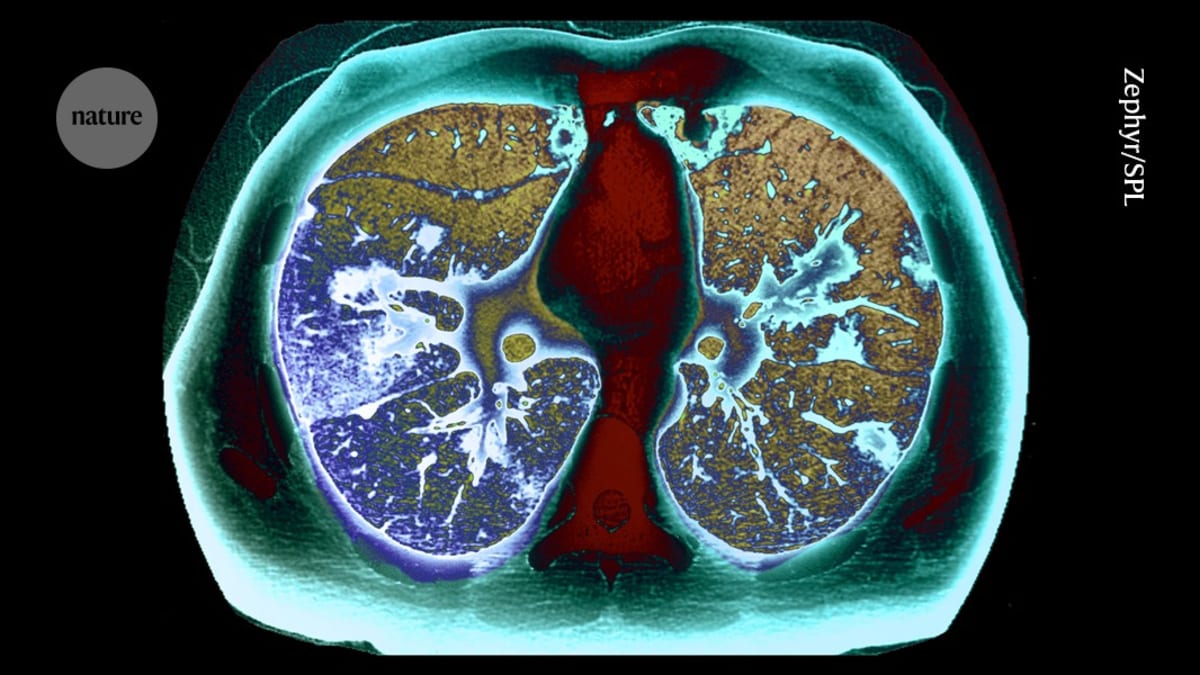

A national lung cancer screening program has transformed early detection rates across the country over the past five years, according to research published in Nature Medicine. The large-scale initiative used CT scans to catch tumors when they're still small and treatable, giving patients dramatically better odds of survival.

Lung cancer remains one of the deadliest cancers worldwide, largely because symptoms often don't appear until the disease has advanced. But this screening campaign flipped that script by actively searching for cancer in high-risk populations before any warning signs emerged.